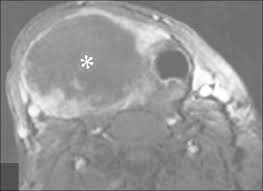

1 5 common misconceptions about thyroid disease Most cases of thyroid cancer affect people between the ages of 20 and 55. If you have a nodule or cyst that gets this big then you may need to have your thyroid gland removed to also take out the nodule/cyst. But the type of cancer is based. Advanced thyroid cancer can make swallowing or breathing difficult if the tumor is exerting pressure on the structures within the neck, says dr.

But the type of cancer is based. If you have a nodule or cyst that gets this big then you may need to have your thyroid gland removed to also take out the nodule/cyst. Thyroid lymphoma quickly develops from the immune system cells. But women are often diagnosed in their 40s and 50s. Although a person can get papillary thyroid cancer at any age, most. It is one of the fastest growing cancer types with over 20,000 new cases a year. Men 2 tumors affecting the thyroid are medullary thyroid cancer. Thyroid cancer is the most dangerous condition of all thyroid problems in men. Papillary thyroid cancer can occur at any age, but most often it affects people ages 30 to 50. If a family member has the mutated gene, they can elect to have preventative treatment, such as surgery to remove the thyroid. Anaplastic thyroid cancer is the most aggressive thyroid cancer. Although it is rare, it is the most common form of endocrine tumour. Some studies have shown that high selenium levels reduce the risk of prostate cancer and that selenium supplements can help prostate cancer;